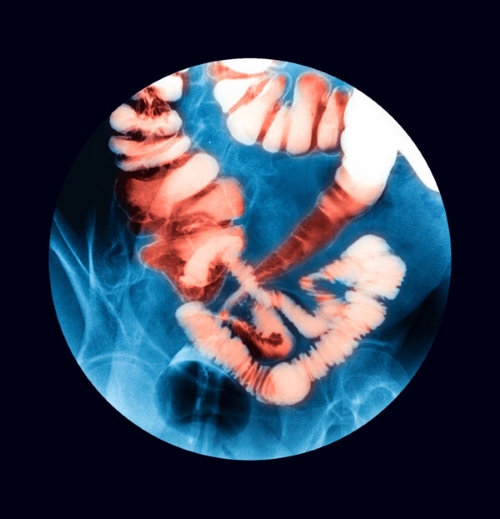

Since they both involve inflammation in the gut, they produce very similar symptoms that include diarrhea, abdominal pain and cramping, fatigue and weight loss. But the two conditions vary in terms of the depth and location of the inflammation.